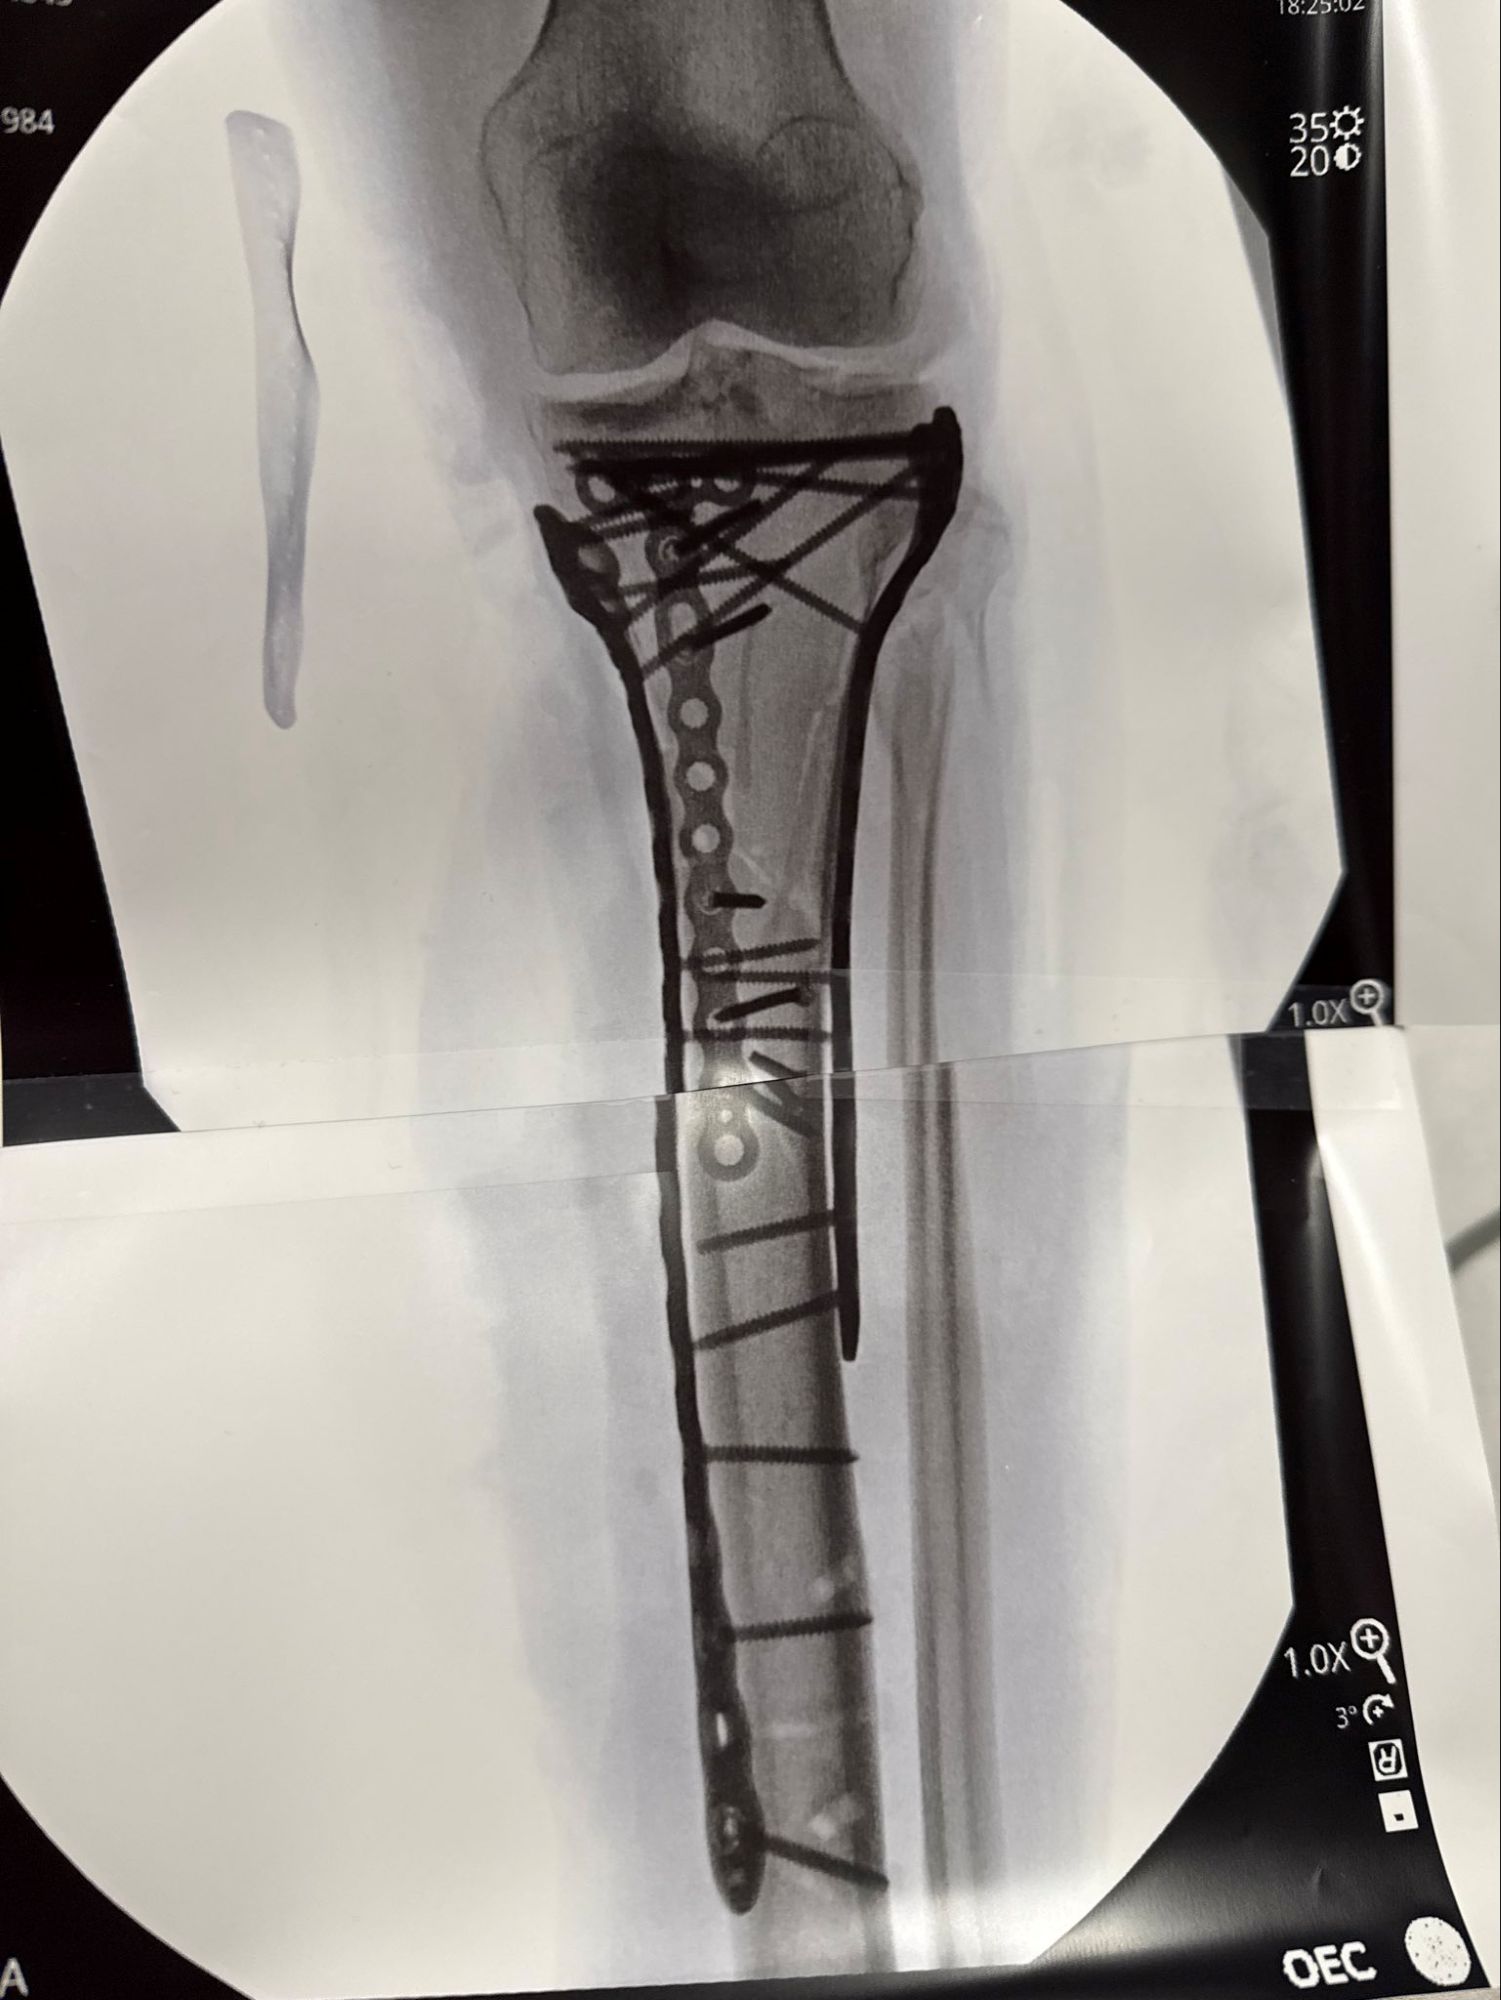

Olympic skier Lindsey Vonn has revealed the extent of her injuries following a serious crash during the 2026 Winter Olympics. In a post on February 20, Vonn shared a graphic X-ray image showing her broken leg, accompanied by a message detailing her recovery process. The incident occurred on February 8, just 13 seconds into her downhill event in Cortina d’Ampezzo, Italy.

Vonn, 41, described her situation as challenging, stating, “I’m bionic for real now.” The X-ray depicted a fractured bone that required multiple plates and screws for stabilization. She praised her surgeon, Dr. Hackett, for his exceptional work and expressed gratitude to Dr. Viola for assisting in the surgery.

Despite the extensive surgical intervention, Vonn indicated that her recovery has been difficult. “With the extent of the trauma, I’ve been struggling a bit post-op and have not yet been discharged from the hospital just yet… almost there. Baby steps,” she explained. Following the accident, she underwent four surgeries in Italy before returning to the United States on February 17 for further procedures.

In an update on her condition, Vonn reported on social media that her last surgery lasted over six hours. “I have been recovering from the surgery but pain has been hard to manage. Making slow progress but I hope I can be out of the hospital soon,” she stated, thanking her supporters for their encouragement.